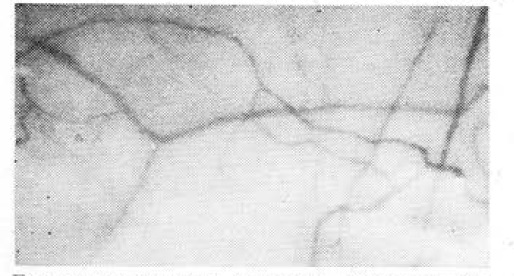

Так, у Е., 19 лет, имеющего разряд легкой атлетике, до тренировки выраженная редукция кровотока: сладжа в сосудах среднего калибра, зернистость кровотока в капиллярах, неравномерность диаметра сосудов, то есть изменения 2.2.КIII(см. рис.). ИГСТ — 55. После специальной тренировки нарушение микроциркуляции — 4.4.KIII , через 1 ч — 3.4.Кш и лишь через 4,5 ч — 2.2.КПІ. На основании этих данных в совокупности с клиническими диагностирована перетренированность. Через 7 дней отдыха показатели микроциркуляции — 1.1.КII, ИГСТ — 84, клинические данные хорошие.

Биомикроскопия сосудов конъюнктивы спортсмена Е., 19 лет. Неравномерность диаметра сосудов, феномен сладжа в сосудах среднего калибра, зернистость кровотока в капиллярах — 2.2.К.Ш.